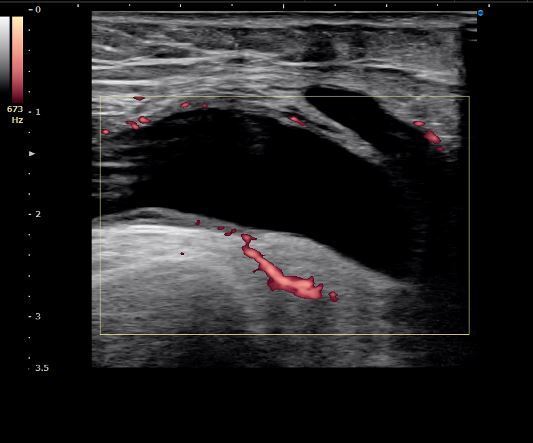

超音波検査

→膝関節の炎症が起こっていることが明確になった 水腫

水腫 血流計測 25mm/sec以上が異常